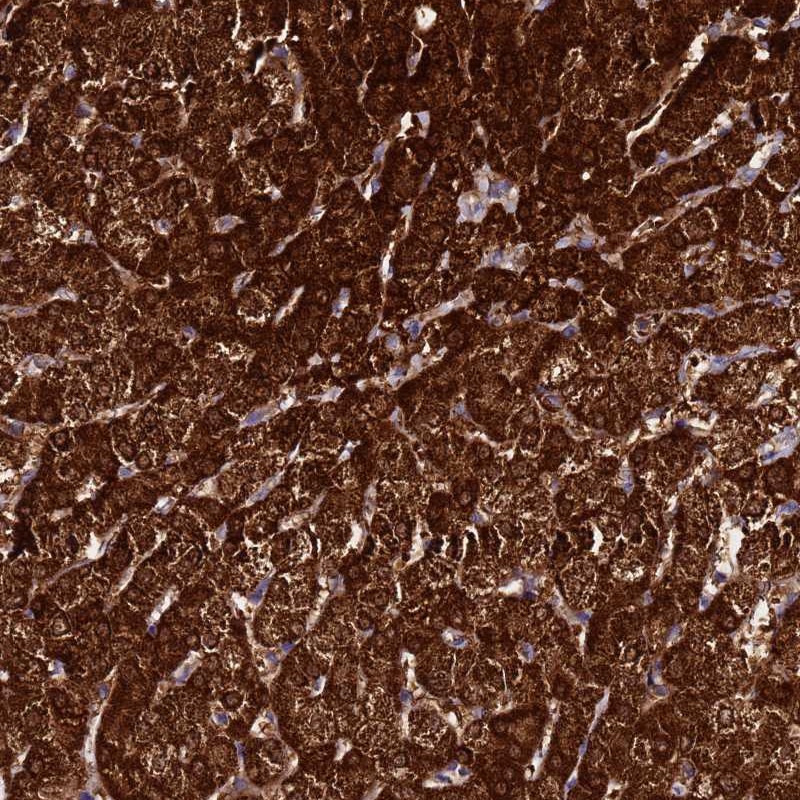

Immunohistochemical staining of human liver shows strong cytoplasmic positivity in hepatocytes.